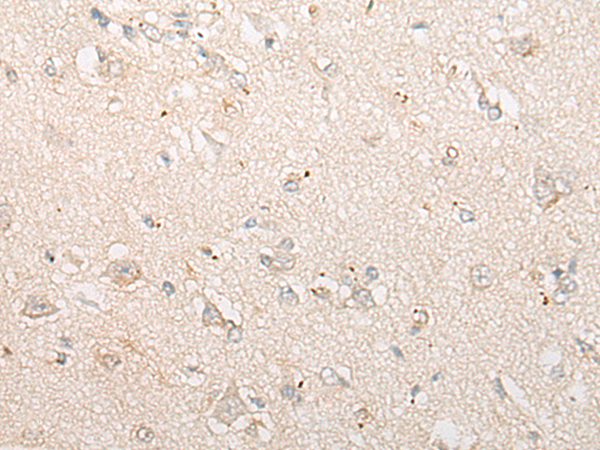

分类: 科研抗体货号: P13219别名: CDP; CUX; p75; CASP; CDP1; COY1; Clox; p100; p110; p200; CUTL1; GOLIM6; CDP/Cut; Cux/CDP; Nbla10317应用: IHC反应种属: Human, Mouse, Rat